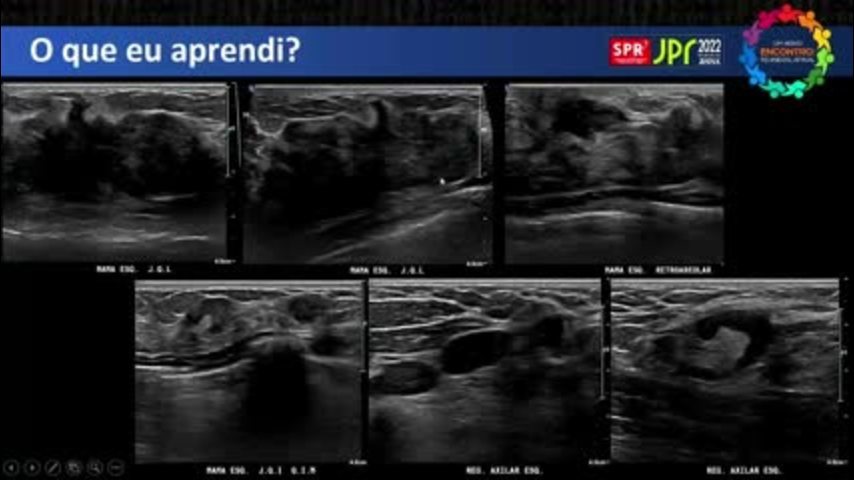

ACR BI-RADS™ na Ultrassonografia: Cas...

ACR BI-RADS™ na Ultrassonografia: Casos em que Tive Dúvidas